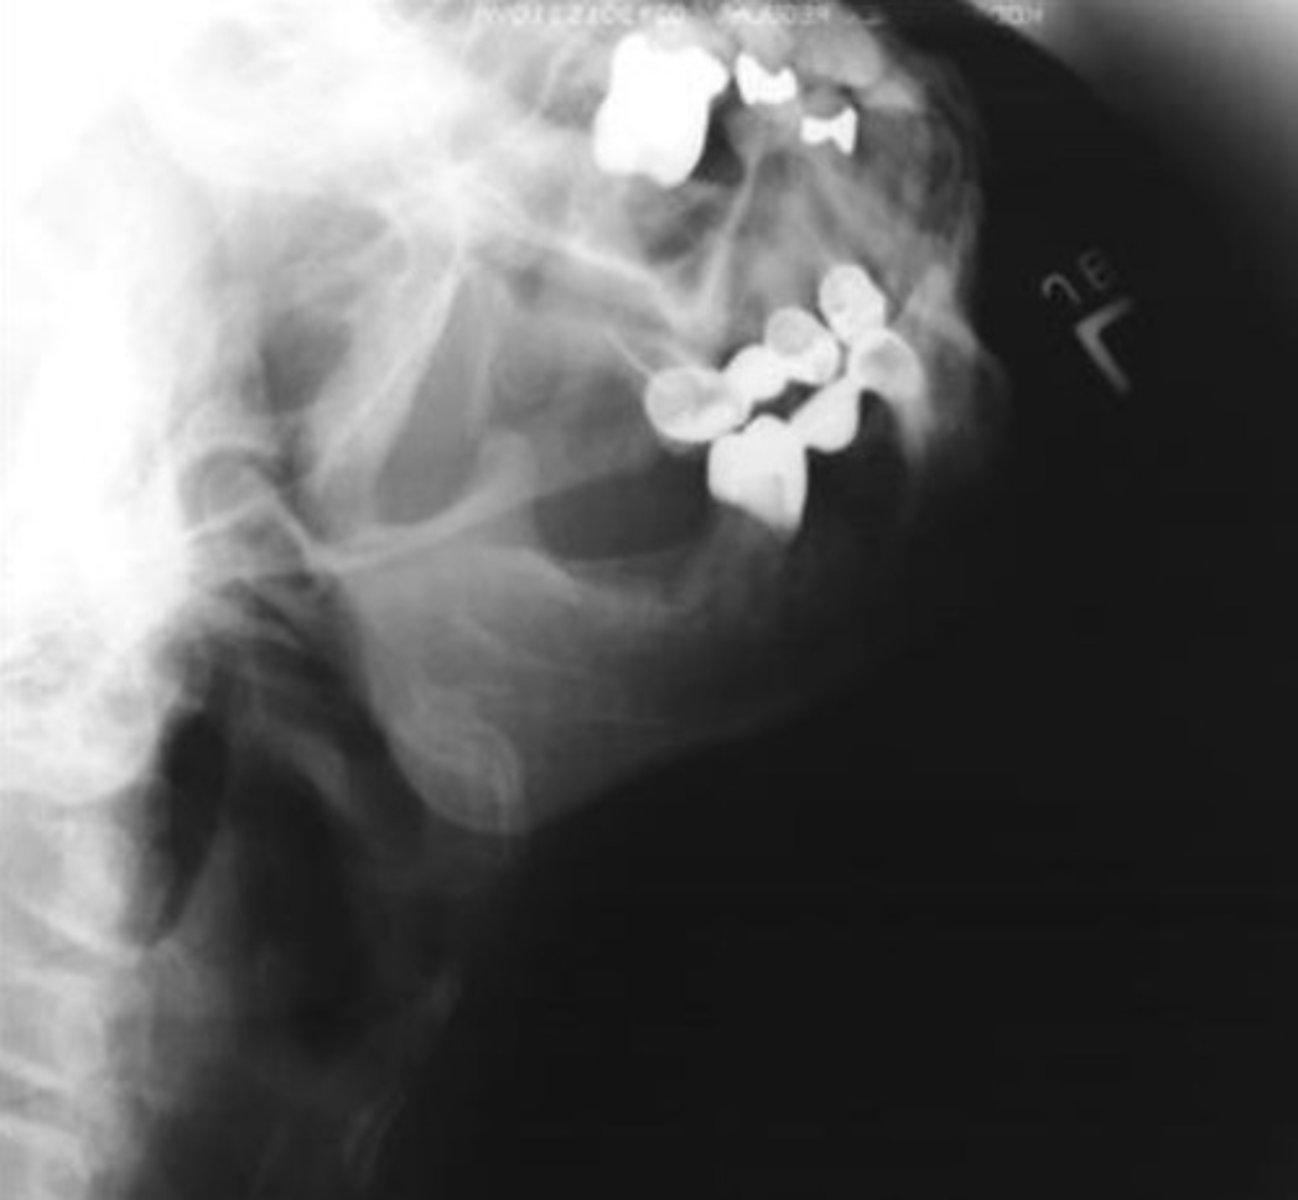

Axiolateral Mandible for Ramus

Name